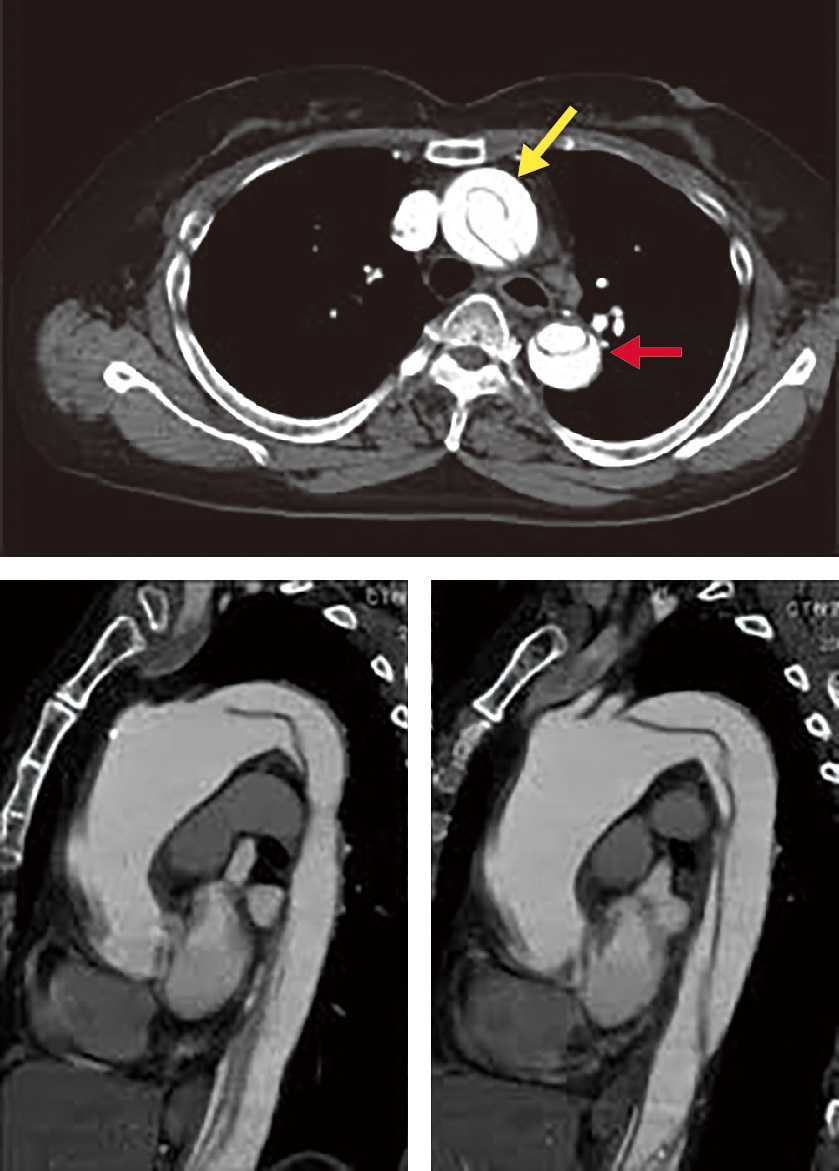

大動脈壁が脆弱化して局所的に全周性または一部が拡張した状態を大動脈瘤とよぶ.一般に,大動脈の外径の直径が正常部位の1.5倍 (目安として胸部大動脈系45 mm,腹部大動脈30 mm) をこえた状態を大動脈瘤と定義する.大部分は無症状のままに経過し,健診や医療機関受診の際の視診や触診,胸部X線写真正面像における縦隔拡大や側面像における拡大,腹部触診や腹部超音波 (図2) やCT (図3),MRI (図4) で発見され診断される.瘤の形状によって,紡錘状あるいは囊状,また壁構造の違いによって,瘤が内膜・中膜・外膜の3層すべてを有する真性動脈瘤と,中膜平滑筋層の連続性が失われ外膜や結合組織によって被包されている仮性大動脈瘤に分類される (図5).大動脈壁脆弱化の原因としては,外傷,梅毒,Marfan症候群などもあるが,最も大きな割合を占めるのは高血圧と加齢に伴う動脈硬化性変化であり,高齢男性に多い.大動脈瘤が解離したり破裂したりすると,激烈な胸背部痛や腹痛を訴えたり,血圧低下しショックに陥ったりする.いったんショック状態に陥った症例はもちろんのこと,病院に搬送されたとしても救命できる可能性は50%以下とされる.瘤径拡大スピードが高いほど,瘤形状が全体的でなく部分的であるほど,また当然,血圧が高いほど破裂リスクは高い.